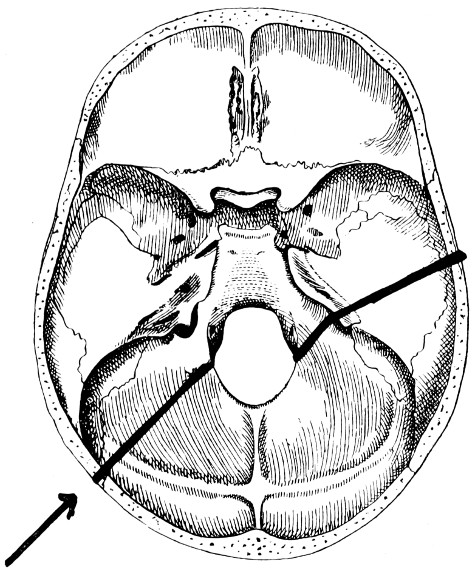

| 32-37. The lines pursued by basic fractures | 83-8 |

| 53. A basic fracture with laceration of both carotid arteries | 148 |

| 54. A basic fracture with laceration of the cavernous sinus | 149 |

| 55. A basic fracture with laceration of both lateral sinuses | 151 |